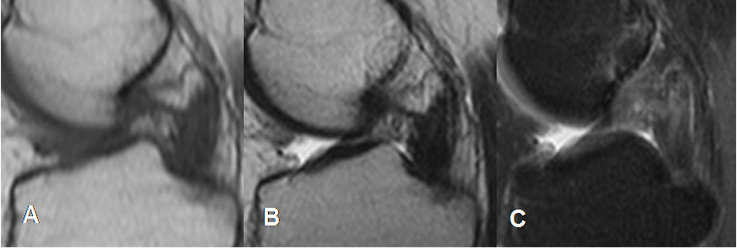

Fig 113. Ruptura del LCP.

A: RM sagital en T1, B: RM sagital en T2 y C: RM sagital en STIR. Ausencia del LCP sin cambios inflamatorios agudos, por ruptura de evolución crónica.

Fig 114. Ruptura del LCP.

A: RM sagital en T1 y B: RM sagital en T2. Solución de continuidad del LCP en su tercio proximal, por ruptura.